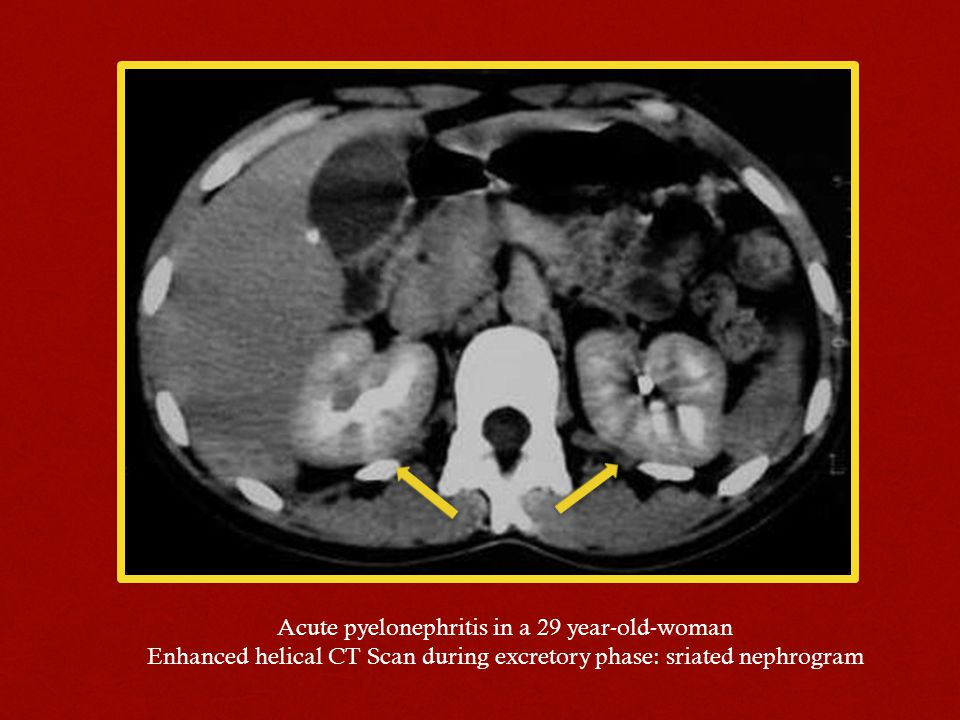

74. 病人主訴發燒和右側腰部疼痛,電腦斷層檢查呈現如圖,下列那一項有關右側腎臟的診斷最 正確?

(A)acute pyelonephritis